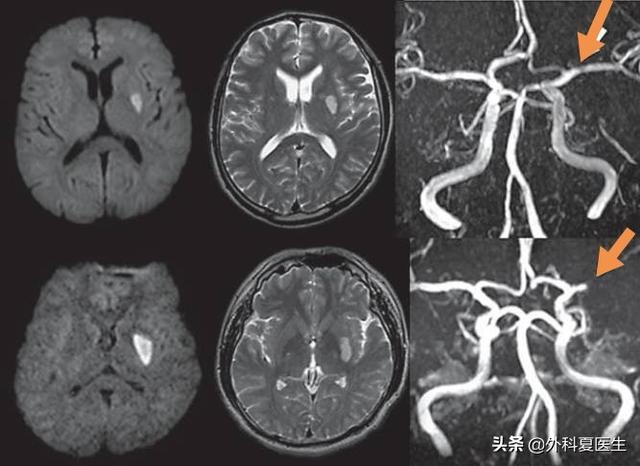

まず、詰まる脳血管が比較的小さく、梗塞領域も比較的小さい。梗塞は通常100ミクロンの血管に発生し、梗塞面積、すなわち病変の大きさは通常1cm以下である。

第二に、ラクナ脳梗塞の部位はより明確であるのに対し、脳梗塞の一般的な部位は不確定である。海綿状梗塞は、主に脳内の穿通動脈(中動脈、後動脈、脳底動脈など)に発生します。したがって、海綿状梗塞の発生部位は、通常、脳の大脳基底核領域、視床、脳橋などである。